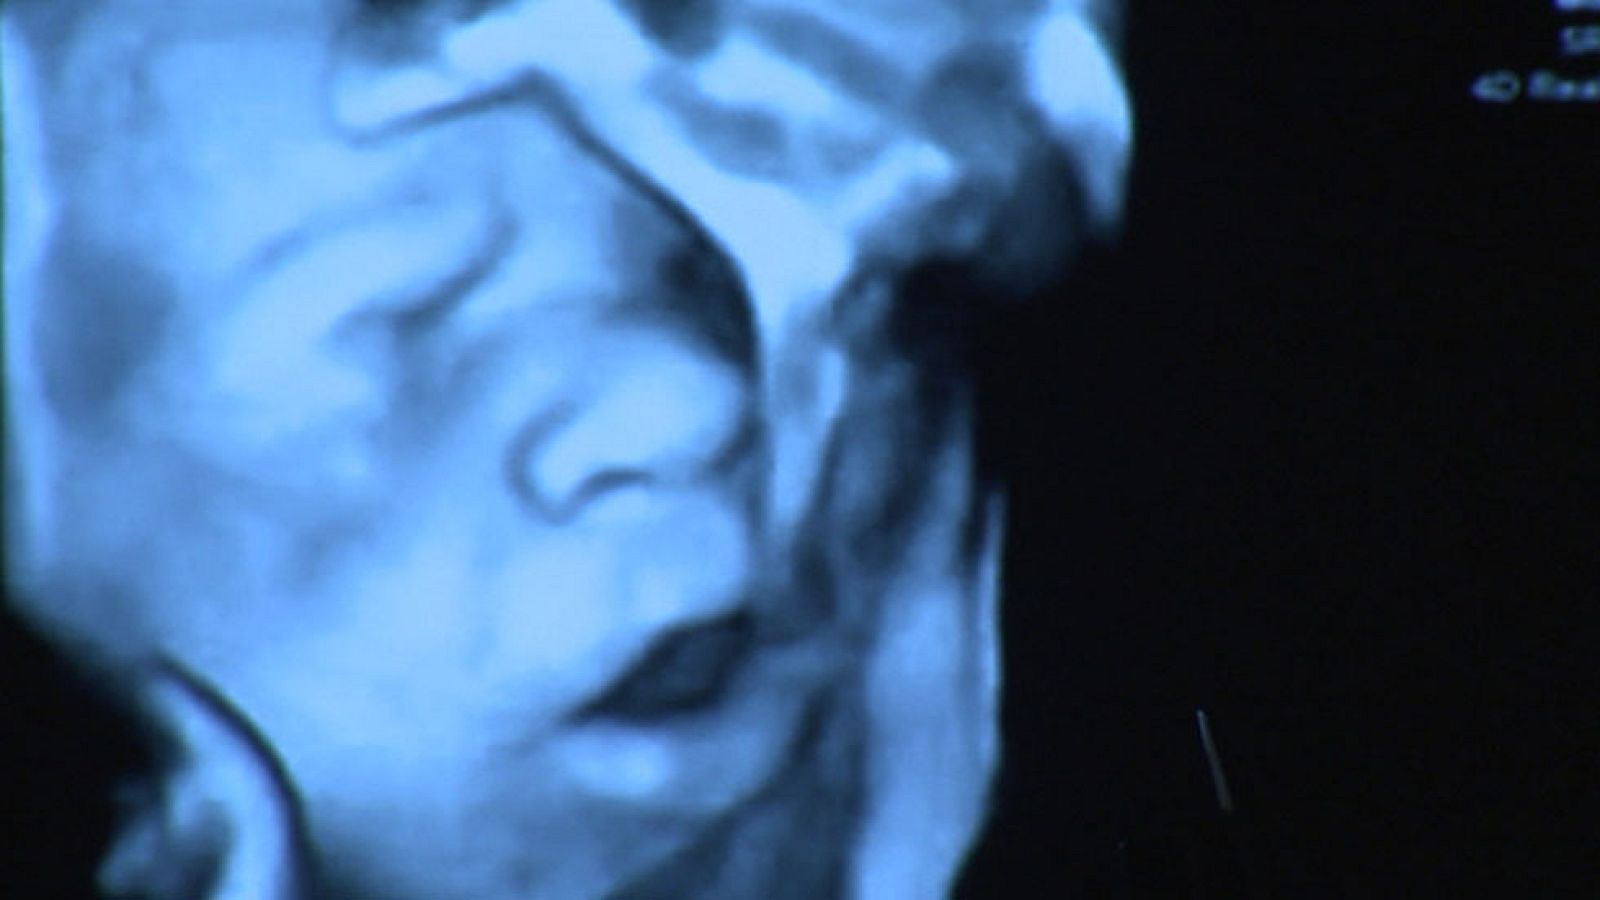

Abren la boca y sacan la lengua, siempre y cuando el sonido llegue desde el interior de la vagina. Así lo ha demostrado un estudio hecho por una clínica de fertilidad en Barcelona, que permite detectar la sordera del feto y que abre nuevas puertas a la investigación.